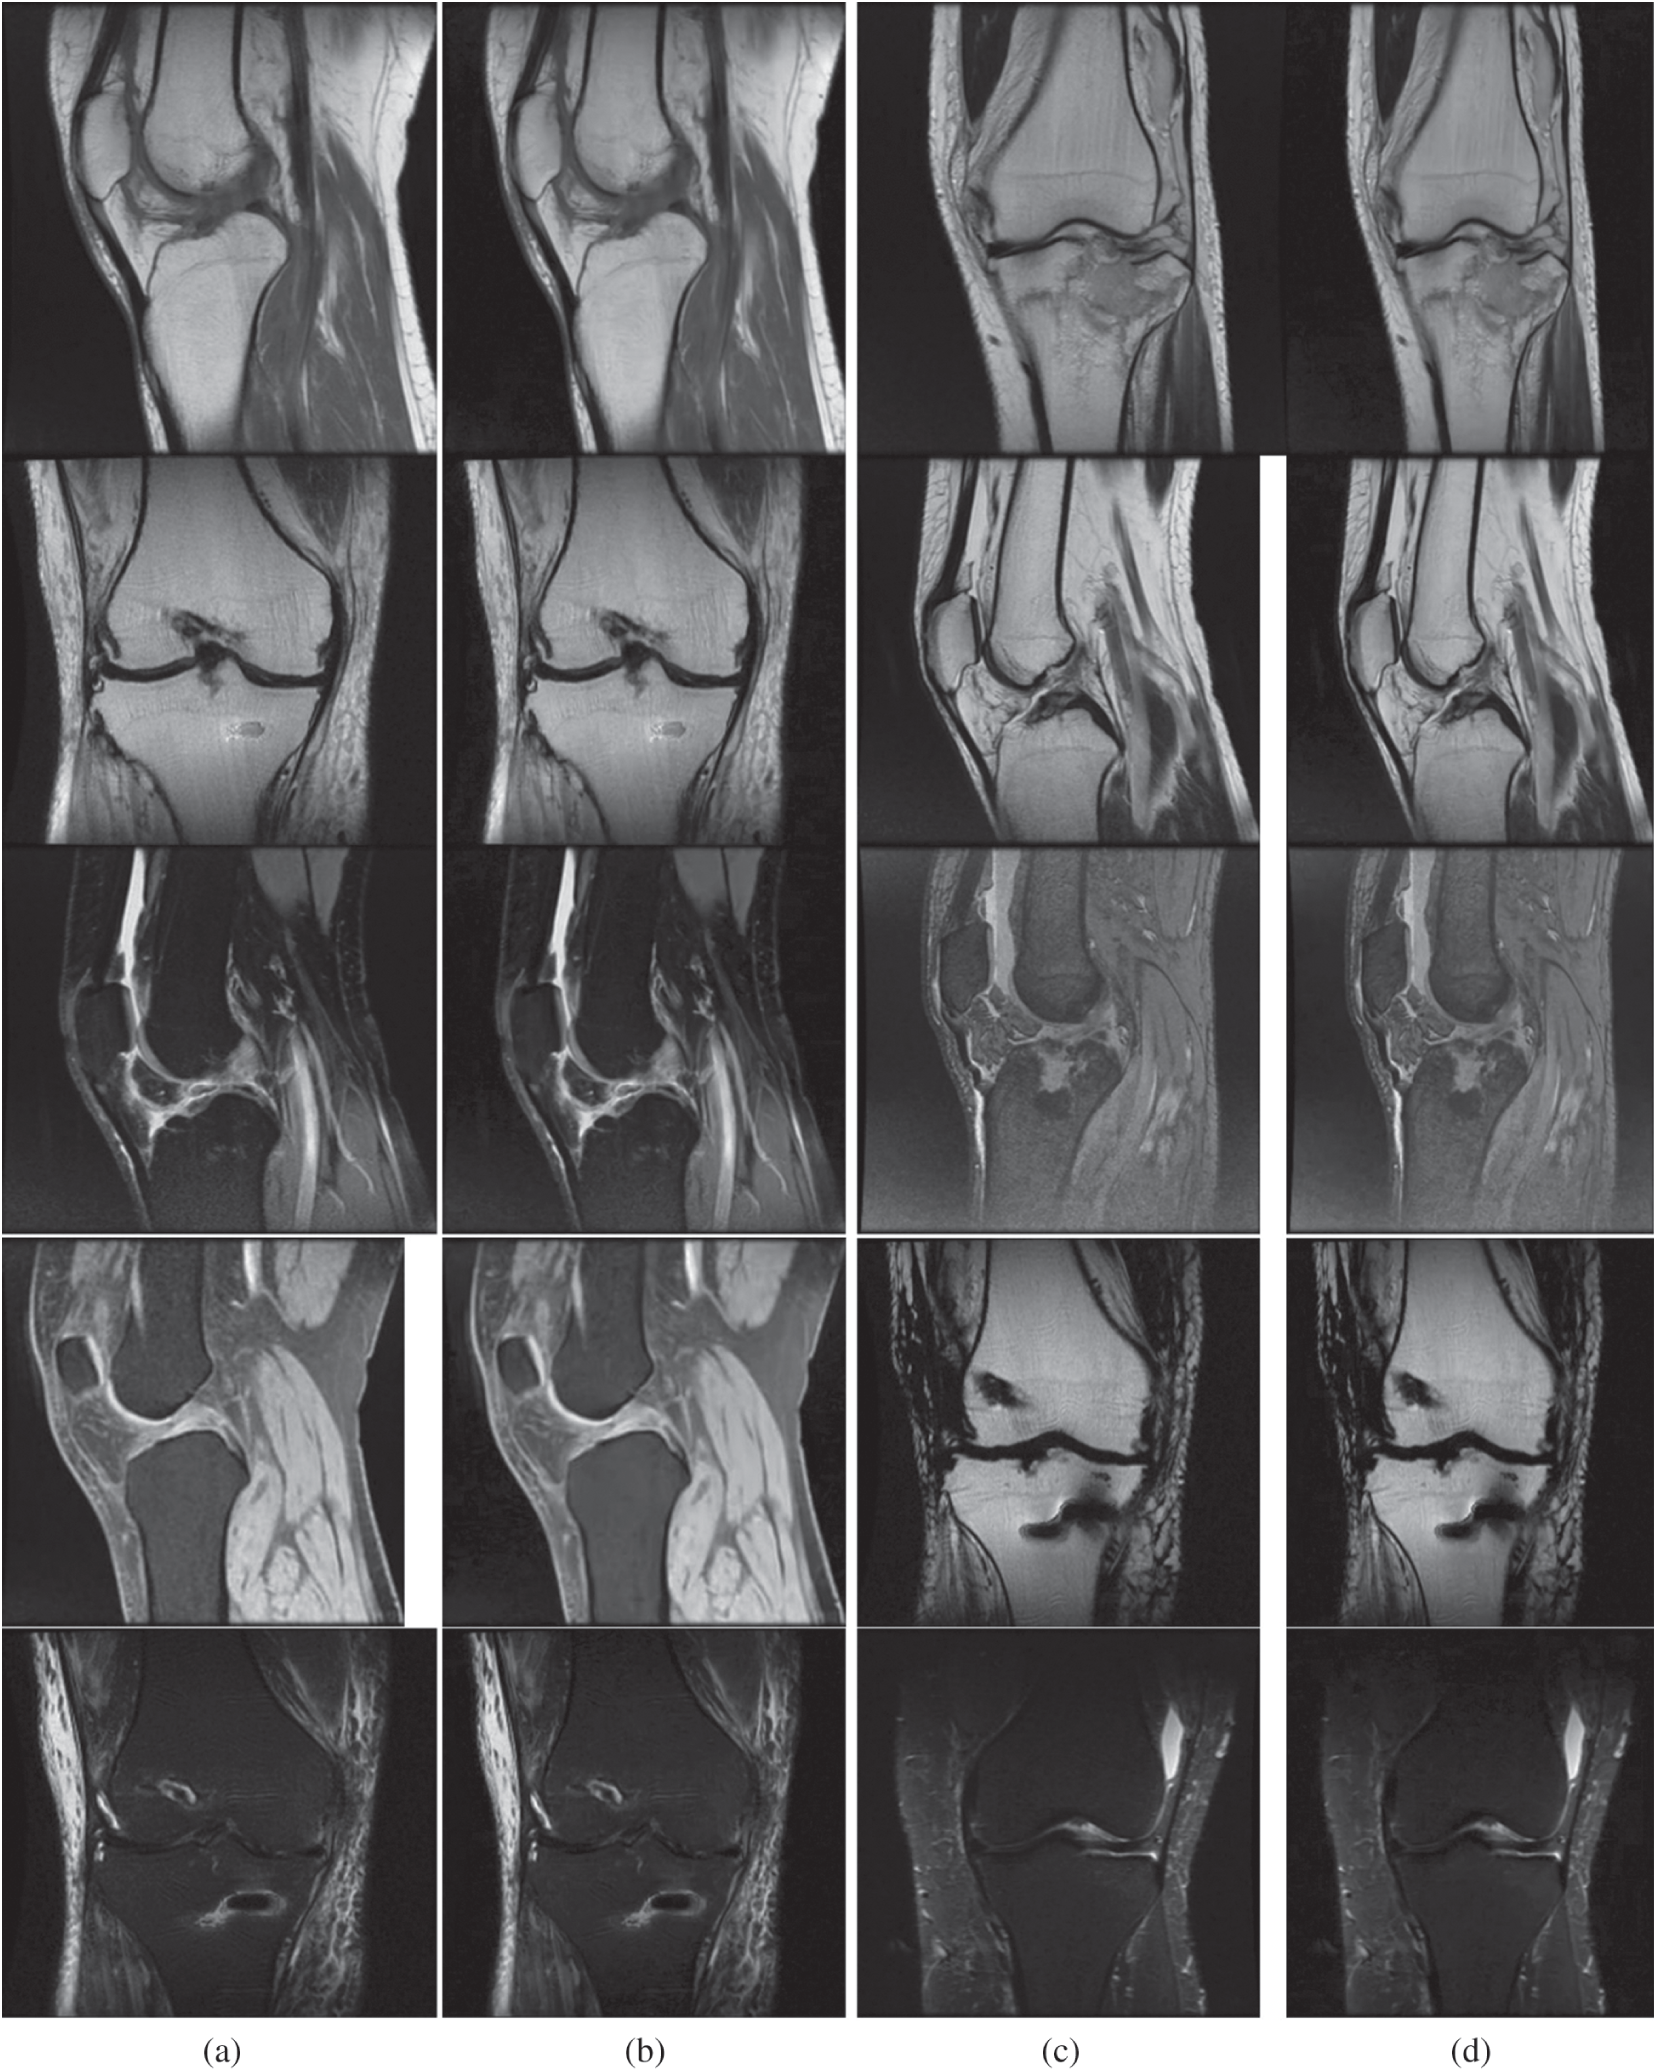

Figure 4: Outcome achieved using the proposed model. Figs. 4a and 4c are medical input images. Similarly, Figs. 4b and 4d are outcomes of the proposed model. The first row represents T1-weighted images, the second row represents FLAIR images and the remaining rows represent T2-weighted images. (a) Input image. (b) Reconstructed image. (c) Input image. (d) Reconstructed image

The experiment was conducted in seven trials and a summary was collected. Fig. 4 discusses the outcomes of the medical images. The first and third columns illustrate the input images, and the second and fourth columns illustrate the outcome of the proposed model. The model has experimented on a few MR images such as: T1-weighted MR images represented in the first row, FLAIR MR images in the second row, and T2-weighted MR images represented in the remaining rows. Tab. 1 describes the PSNR, where our proposed model provided an outcome of more than 40 dB for all trails. Tab. 2 provides information regarding the SSIM of the proposed model and compared it with different methods. The proposed model exhibited an SSIM value of 0.87 ± 0.08 which was best among other compared methods. Tab. 3 provides information regarding the MSE, exhibiting that our model gave the least error compared with others. Tab. 4 discusses the computational time required for the overall processing of the image. The proposed model processed with an approximate time of 96 s.